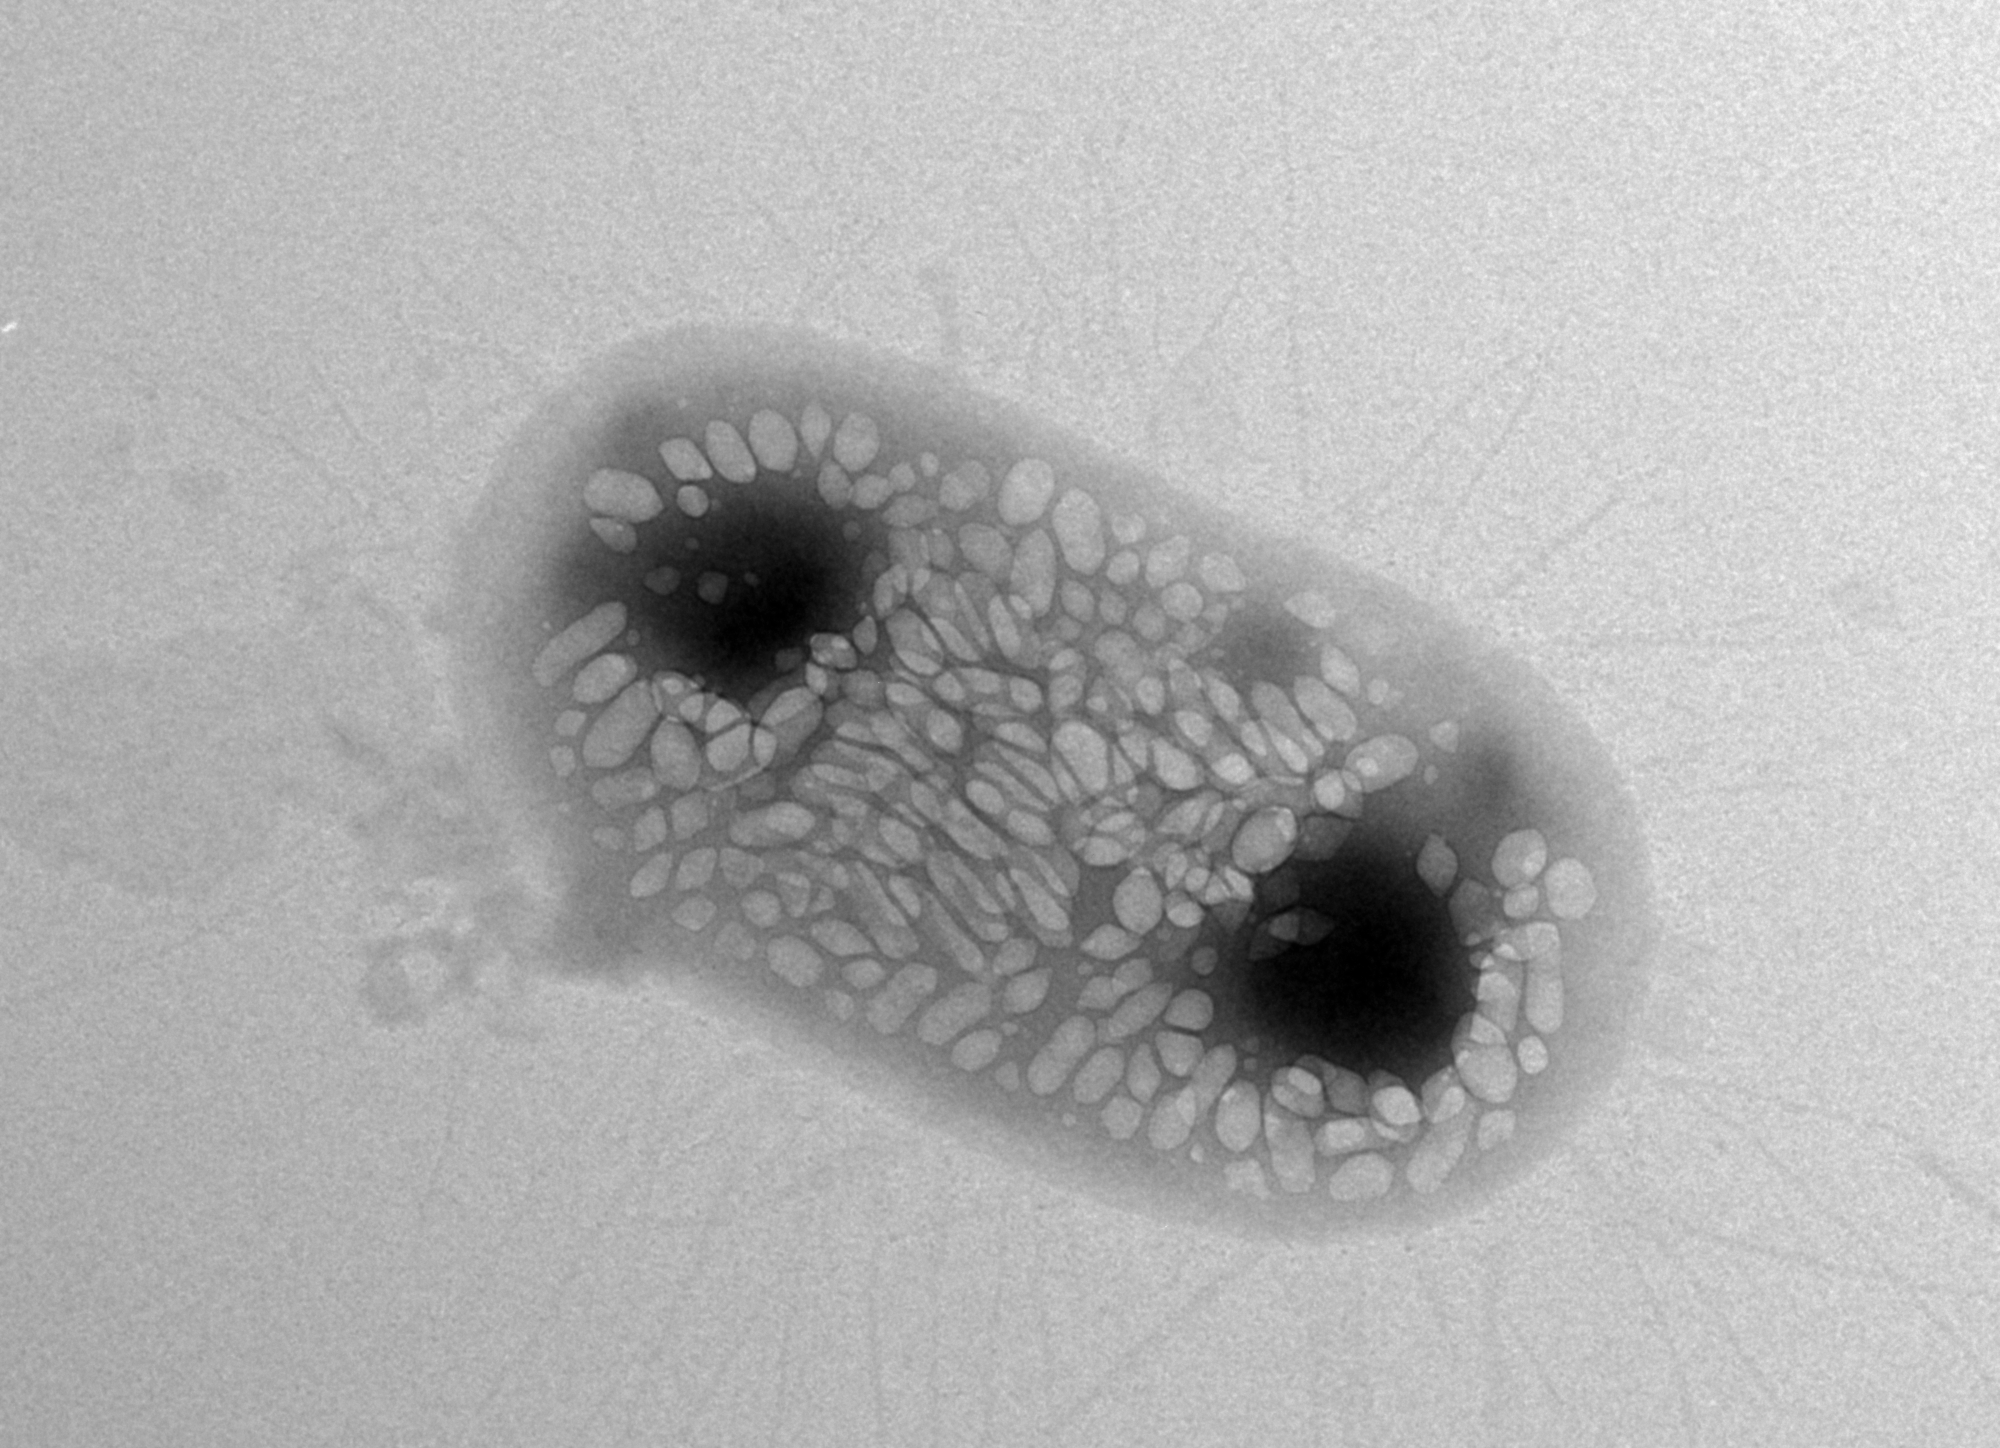

Shapiro wants to solve this problem with ultrasound techniques because sound waves can travel deeper into bodies. He says he had a eureka moment about six years ago when he learned about gas-filled protein structures in water-dwelling bacteria that help regulate the organisms' buoyancy. Shapiro hypothesized that these structures, called gas vesicles, could bounce back sound waves in ways that make them distinguishable from other types of cells. Indeed, Shapiro and his colleagues demonstrated that the gas vesicles can be imaged with ultrasound in the guts and other tissues of mice.

One of the challenges the team hit involved the transfer of the genetic machinery for gas vesicles into E. coli. They first tried to transfer gas-vesicle genes isolated from a water-dwelling bacterium called Anabaena flos-aquae, but this didn't work—the E. coli failed to make the vesicles. They tried again using gas-vesicle genes from a closer relative of E. coli, a bacterium called Bacillus megaterium. This didn't succeed either, because the resulting gas vesicles were too small to efficiently scatter sound waves. Finally, the team tried a mix of genes from both species—and it worked. The E. coli made gas vesicles on their own.

The gas vesicle genes code for proteins that act like either bricks or cranes in building the final vesicle structure—some of the proteins are the building blocks of the vesicles while some help in actually assembling the structures. "Essentially, we figured out that we need the bricks from Anabaena flos-aquae and the cranes from Bacillus megaterium in order for the E. coli to be able to make gas vesicles," says Bourdeau.